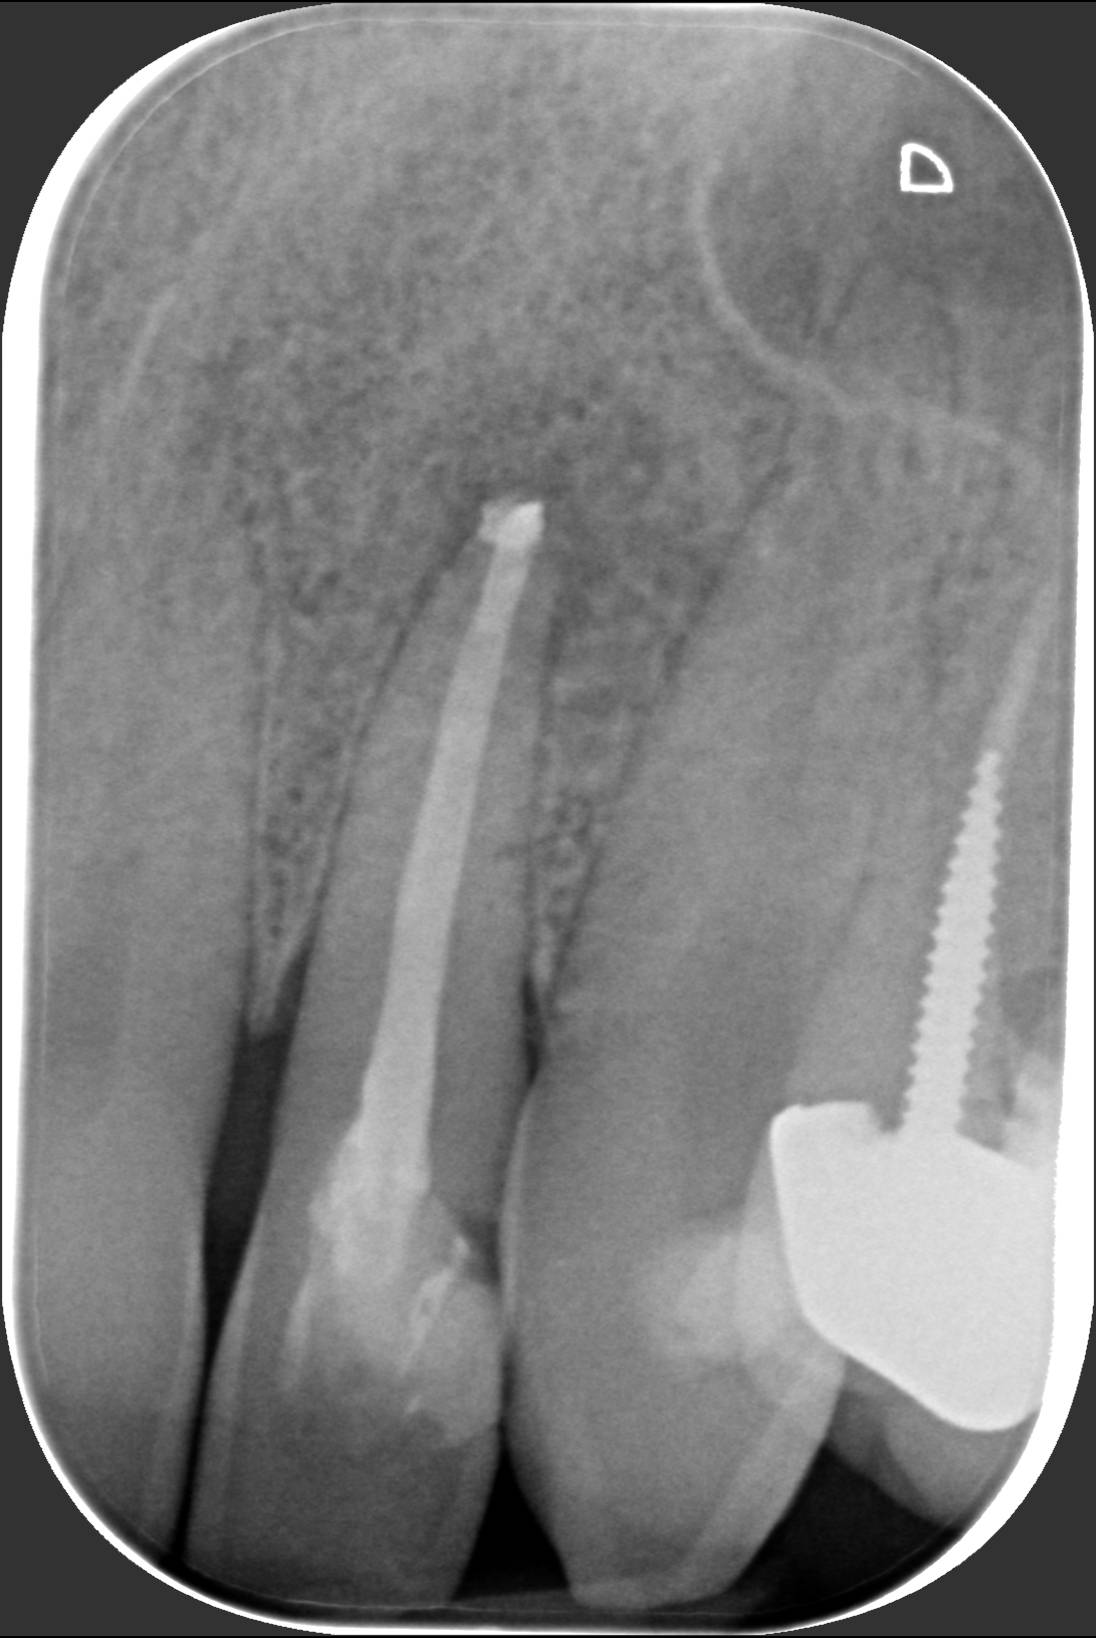

Il dentista ti dice che deve curarti tramite terapia canalare. Ti sei chiesto cosa succederà al tuo dente? All’interno del dente c’è un nervo. Se ne accorge chi ha una carie profonda: quando si infiamma fa un male insopportabile. Il classico mal di denti deriva proprio da qui. Non c’è farmaco che tenga, bisogna devitalizzare il dente malato, cioè togliergli il nervo. Ma non basta. Bisogna poi allargare lo spazio fino alla radice per pulire alla perfezione i residui del tessuto pulpare, dove era inserito il nervo. Si usano strumenti manuali e rotanti, montati su speciali “trapani”. Successivamente si eseguono numerosi lavaggi con siringhe di disinfettante. Alla fine bisogna chiudere tutto lo spazio creato con materiali speciali, che sigillano tutta la lunghezza del canale in modo tridimensionale. Dalla radiografia si vede se il lavoro è stato effettuato in modo corretto: l’otturazione canalare è quella striscia bianca che percorre tutta la lunghezza della radice, come vedi nella prima foto. Se invece si ferma a metà canale, come nella seconda foto, il lavoro non è eseguito a regola d’arte. Questo può portare al “granuloma”, un’infezione dell’apice del dente. In questo caso bisogna fare una nuova terapia canalare, eseguendo un “ritrattamento canalare”, togliendo la precedente otturazione canalare, ripulendo tutto, e otturando il canale fino in fondo, come si vede nella prima foto. Qui a Besana Brianza, il dott. Fabio Ballestrasse e il suo collaboratore dott. Vergani eseguono le terapie canalari come nella prima foto.